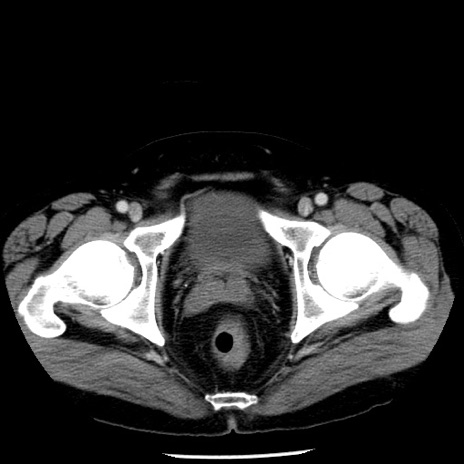

冠状断像

【症例】40歳代男性

【現病歴】2日前から胃痛あり。徐々に周期的な激痛に変化した。本日になっても激痛があるため受診。

【身体所見】意識清明、BT 38-39℃台あり、腹部:膨満、やや硬、右下腹部に圧痛あり。

【データ】WBC 8500、CRP 23.26